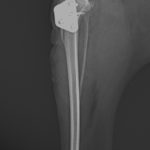

膝蓋骨内方脱臼 グレード4

小型犬の膝蓋骨内方脱臼(MPLグレード4)に対する整復依頼があった。徒手によって膝蓋骨が大腿骨滑車内に完納しない、つまり重症である。BRTにより大腿骨滑車形成術を行い、内側広筋の筋膜リリース、パテラを滑車に戻した状態で余剰関節包の再建術を実施。脛骨粗面を骨切り、大腿四頭筋〜膝蓋骨〜脛骨粗面〜足根関節のアライメント調整を行い仮固定ピンによりT.T.Tの移動幅を決定。5.0mmのスパイク形状のスペーサーでLateralizationを行った。1.5 Staggered Locking Patella Plate for T.T.Tを利用し、強固に粗面の固定術を実施。最後に骨切り部位にBRTで得られた海綿骨を移植し終了。日本ではまだ馴染みの少ない術式ではあるが、ドイツを中心にヨーロッパにおいて認知されはじめている。